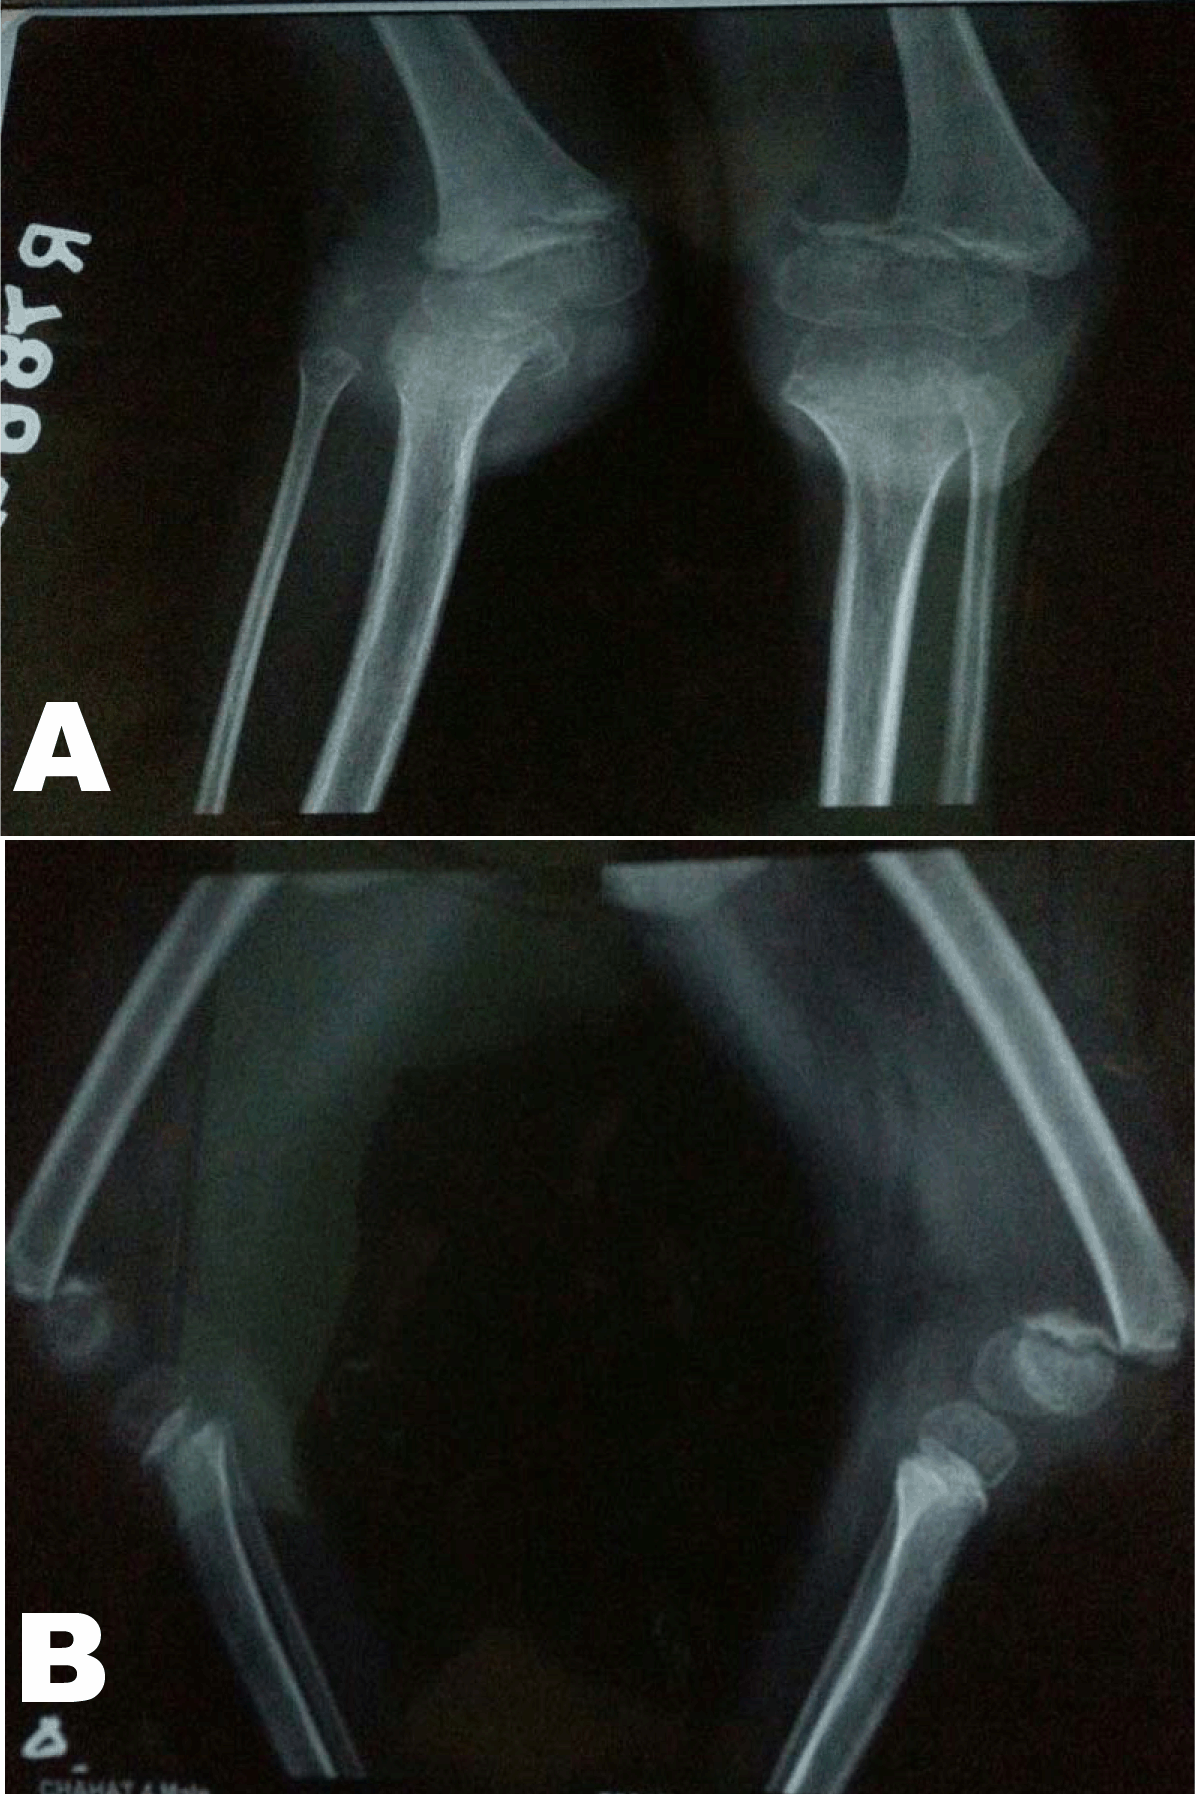

Radiographs of bilateral knees were taken. (Figure 2) These demonstrated bilateral Salter–Harris type 1 physeal injuries. Routine laboratory investigations were essentially normal except for anaemia (hemoglobin 9.8) and mildly raise alkaline phosphatase (ALP-564). Calcium profile was normal, so were serum vitamin C levels (0.84 mg/dL).

Figure 2: (A, B) Anteroposterior and Lateral X-rays of knee showing bilateral slips.